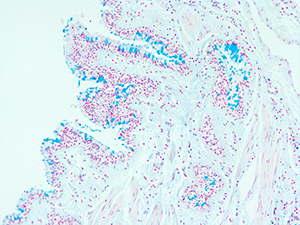

31 Year Old Adult Human Lung DD034L H&E